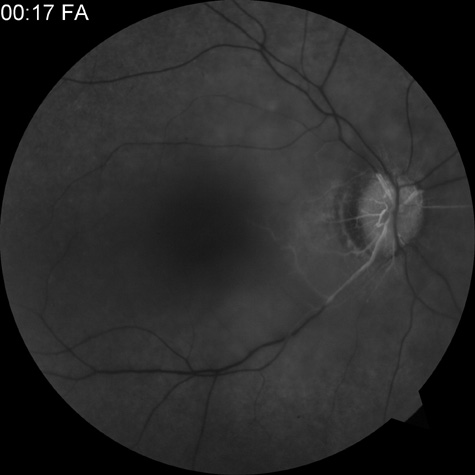

When a branch retinal artery is obstructed, there is usually whitening of the retina in the area supplied by the artery (Fig. 2). In most eyes (62% in one series), emboli are responsible for the obstruction.94 The temporal branch arteries are involved in almost all cases that have been reported,92,94 but whether this is because nasal branch retinal artery obstructions are rare or because such obstructions are simply asymptomatic is unknown. The characteristics of a branch retinal artery obstruction on intravenous fluorescein angiography are similar to those for central retinal artery obstruction.